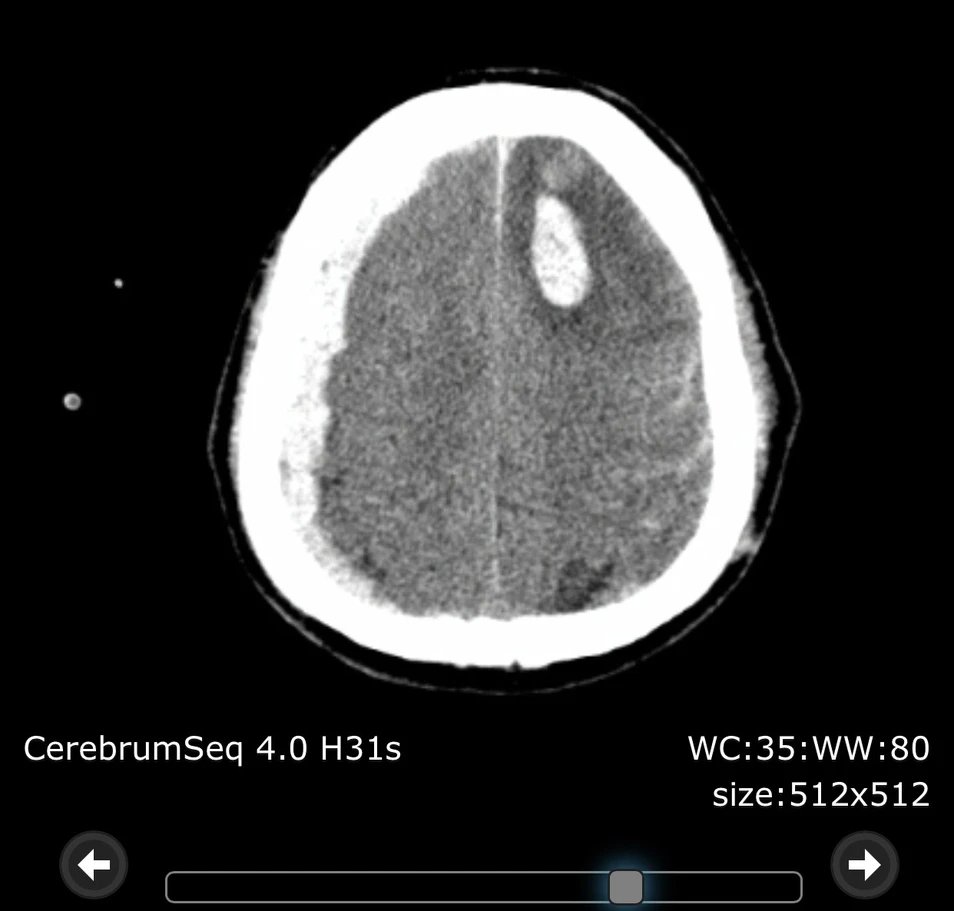

Sau khi được các y, bác sĩ của Bệnh viện Đa khoa thành phố Vinh thăm khám, thực hiện các cận lâm sàng, bệnh nhân được chẩn đoán hôn mê do chấn thương sọ não: dập não đa ổ, tụ máu dưới màng cứng cấp bán cầu phải do tai nạn giao thông; xơ gan rối loạn chức năng đông máu.

Ảnh chụp CT scanner sọ não trước khi phẫu thuật.